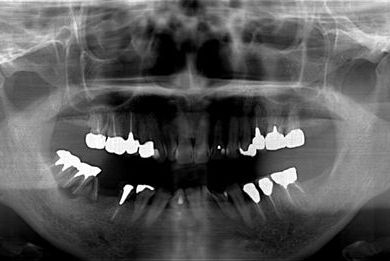

抜歯即日スピードインプラント+セラミック治療

| 治療方針 | 抜歯と土井jにインプラントを埋入し、治療期間を短縮する。 | ||||||||||||||||||||||||||||||||

| 治療内容 | インプラント2本(抜歯即日スピードインプラント)、ハイブリッドセラミッククラウン5本(セラミック用土台2本)、ハイブリッドセラミックインレー1本 | ||||||||||||||||||||||||||||||||

| 総治療費 | 1,052,783円 | ||||||||||||||||||||||||||||||||

| 治療期間 | 1年3ヶ月 |